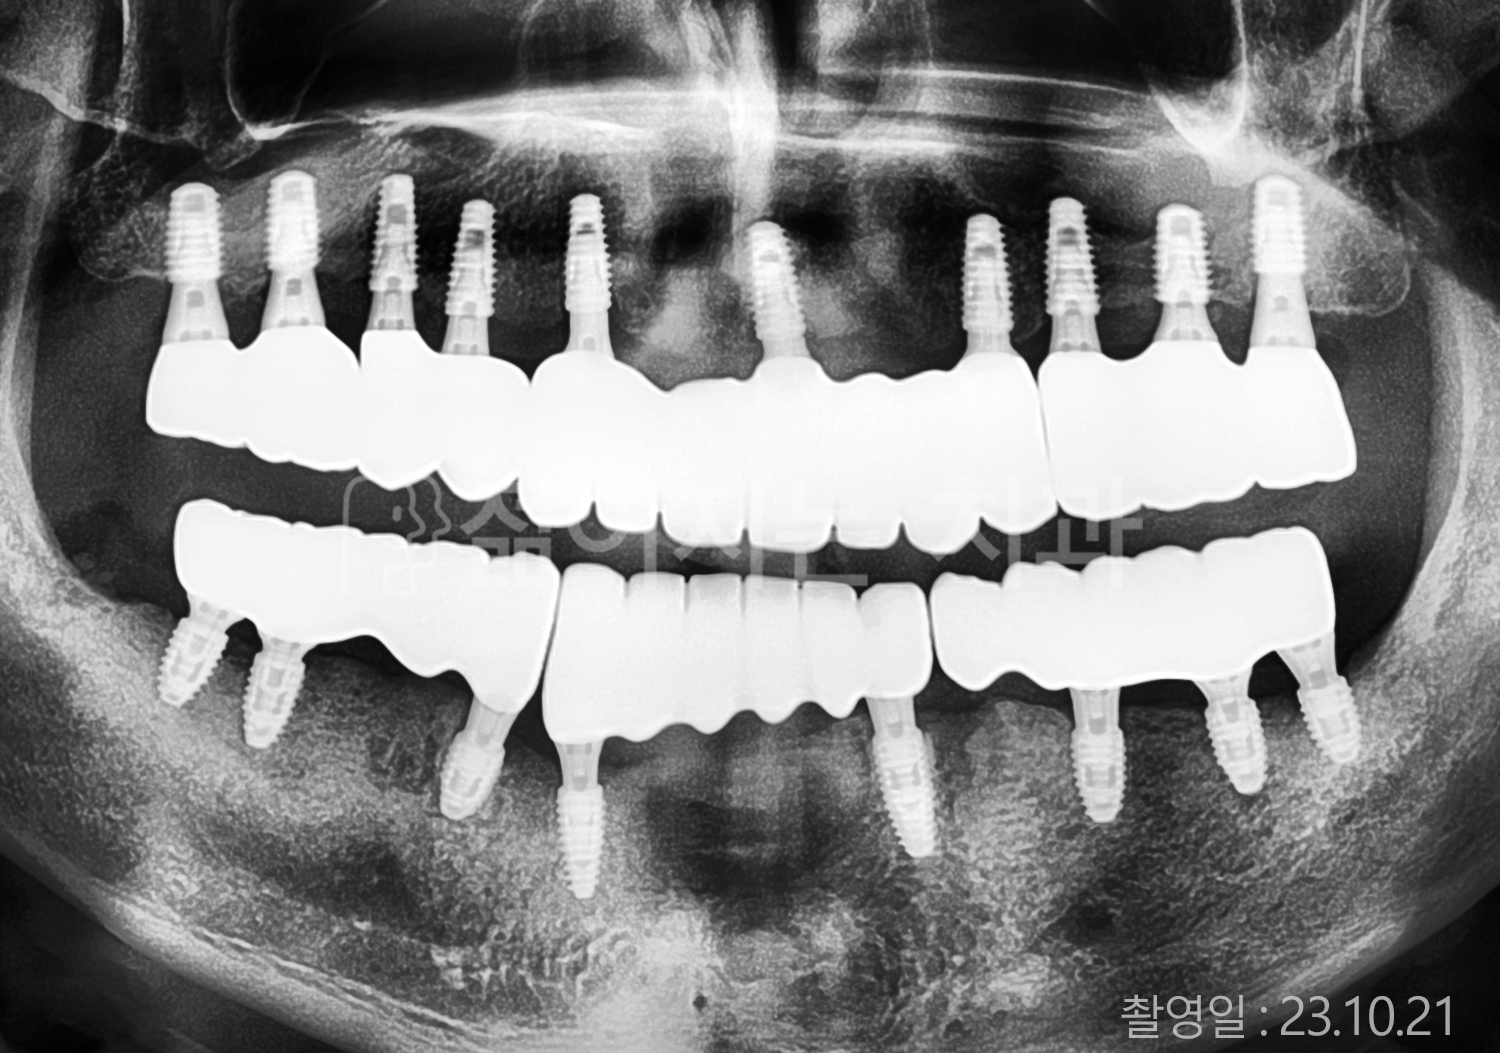

• 70대 고혈압, 고지혈증 전체치아 10개 이상 임플란트

• 60대 당뇨, 간염 전체치아 10개 이상 임플란트

• 80대 골다골증 전체치아 6개 이상 임플란트

• 70대 고혈압, 당뇨 전체치아 10개 이상 임플란트

• 60대 간 질환 전체치아 10개 이상 임플란트

• 60대 전체치아 10개 이상 임플란트

• 70대 전체치아 10개 이상 임플란트

• 50대 전체치아 10개 이상 임플란트